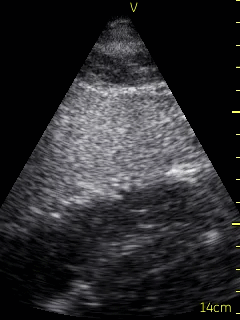

A transthoracic echo (TTE) was ordered for the morning following admission, and a bedside echocardiogram was conducted with a hand-held ultrasound unit (VScan, GE), revealing a dilated hypokinetic right ventricle and grossly normal left ventricular systolic function. The point-of-care cardiac ultrasound (POCUS) led to a new Differential: PE and ACS/right ventricular infarct.